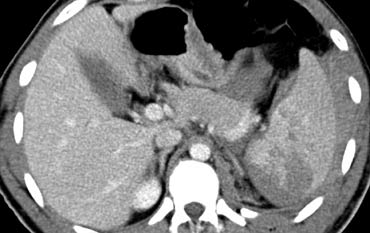

Trước tiên hãy quan sát các hình ảnh bên trái của bệnh nhân bị chấn thương gan.

Mô tả các dấu hiệu hình ảnh.

Sau đó tiếp tục.

Các dấu hiệu bao gồm:

- Mũi tên xanh lá: vùng giảm tỷ trọng hình bầu dục phù hợp với tụ máu

-

Mũi tên vàng: vùng giảm tỷ trọng hình tuyến tính phù hợp với đường rách.

Lưu ý rằng đường rách này đi qua nhánh trái của tĩnh mạch cửa - Mũi tên xanh dương: vùng giảm tỷ trọng mờ, ranh giới không rõ phù hợp với dập gan

- Dịch quanh gan

- Gần như có sự đứt ngang hoàn toàn của gan, nhưng cả hai thùy đều còn ngấm thuốc, cho thấy nguồn cung cấp mạch máu vẫn còn bình thường.